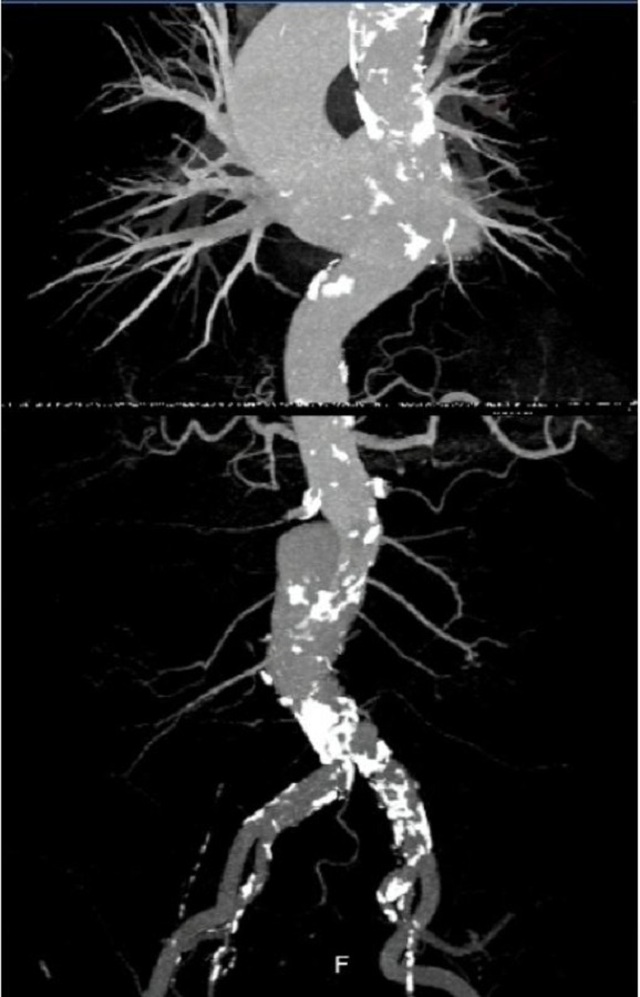

Hình ảnh động mạch chủ của người bệnh trên hệ thống chụp mạch máu xóa nền thời điểm trước can thiệp

Với sự hỗ trợ của hệ thống chụp mạch máu xóa nền, ê kíp bác sĩ đã đặt thành công stent vào vị trí túi phình động mạch chủ bụng cho người bệnh. Thiết bị là một khung giá đỡ bằng kim loại được phủ bởi màng sợi tổng hợp trong lòng của túi phình để tái tạo thành động mạch bị tổn thương, đồng thời điều chỉnh dòng chảy đúng sinh lý hơn, ngăn chặn nguy cơ vỡ túi phình. Sau can thiệp, sức khỏe bệnh nhân bình phục rất tốt.